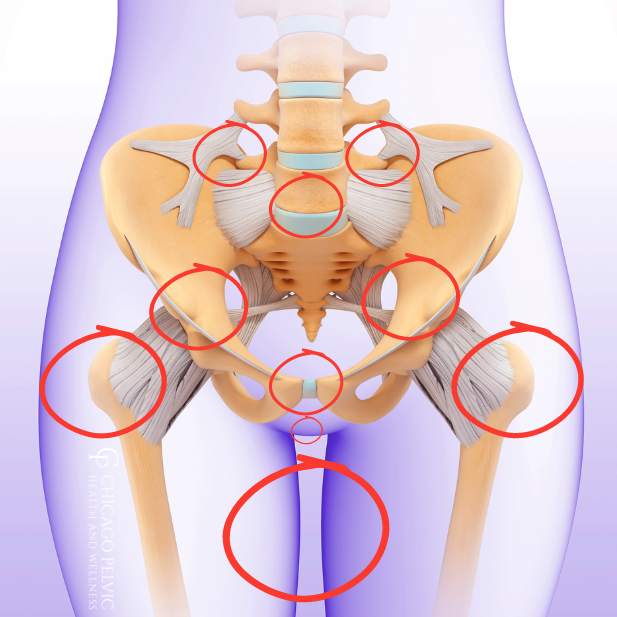

গর্ভাবস্থায় পেলভিক গার্ডল পেইন হলো এমন এক ধরনের ব্যথা যা পেলভিস বা কোমরের নিচের অংশে দেখা যায়। এই ব্যথা হিপ জয়েন্ট, তলপেট, কোমর, এমনকি উরু পর্যন্ত ছড়িয়ে পড়তে পারে। এটি গর্ভাবস্থার দ্বিতীয় বা তৃতীয় ট্রাইমেস্টারে বেশি দেখা যায়।

গর্ভাবস্থায় পেলভিক গার্ডল পেইন হওয়ার পেছনে কয়েকটি গুরুত্বপূর্ণ কারণ রয়েছে:

- হরমোনাল পরিবর্তনের ফলে লিগামেন্টগুলো নরম হয়ে যায়

- শিশুর ওজন বেড়ে যাওয়ায় পেলভিসের ওপর চাপ বৃদ্ধি

- মায়ের শরীরের ভরকেন্দ্র পরিবর্তন

- পূর্বে কোমর বা পেলভিসে আঘাত পাওয়া

- বেশি সময় দাঁড়িয়ে থাকা বা ভারী কাজ করা

এই সব কারণে পেলভিক এলাকার জয়েন্টগুলো ঢিলা হয়ে গিয়ে ব্যথা ও অস্বস্তি তৈরি করে।